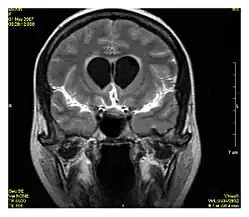

Neuroimaging

MRI is the investigative tool of choice for neurological cancers over CT, as it offers better visualization of the posterior cranial fossa, containing the brainstem and the cerebellum. The contrast provided between grey and white matter makes MRI the best choice for many conditions of the central nervous system, including demyelinating diseases, dementia, cerebrovascular disease, infectious diseases, Alzheimer's disease and epilepsy.[31][32][33] Since multiple images are taken milliseconds apart, it can show how the brain responds to different stimuli, enabling researchers to study both functional and structural brain abnormalities in psychological disorders.[34] MRI also is used in guided stereotactic surgery and radiosurgery for treatment of intracranial tumors, arteriovenous malformations, and other surgically treatable conditions using a device known as the N-localizer.[35][36][37] New tools that implement artificial intelligence in healthcare have demonstrated higher image quality and morphometric analysis in neuroimaging with the application of a denoising system.[38]